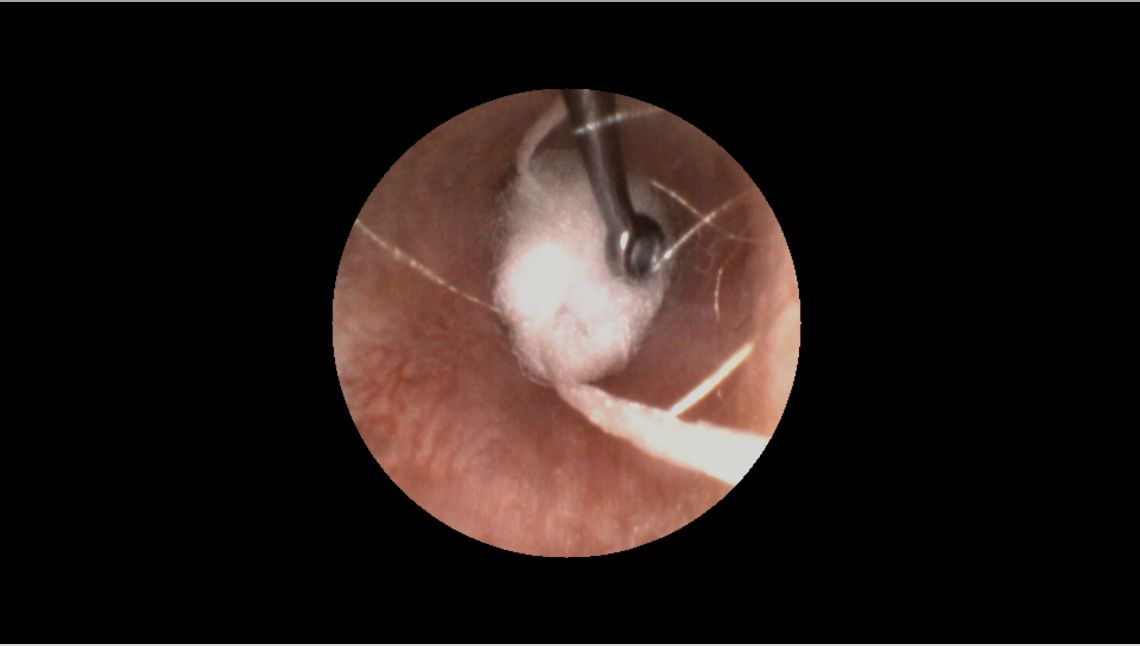

- Use your otoscope and a curette to guide the block past the second bend of the ear canal and place it as close as possible to the eardrum.

- Once placed, check your work by inspecting the perimeter of the otoblock with your otoscope to ensure there are no gaps.